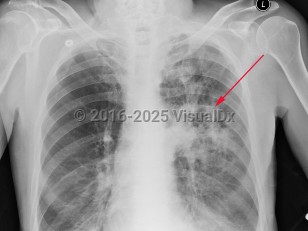

Chest pain, Pleural effusion, 50-59 year old Female

Pleural effusionPleural effusion

Congestive heart failureCongestive heart failure

Pulmonary edema